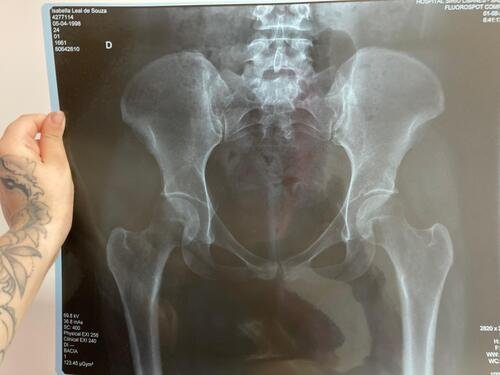

Meu nome e Isabella, mais conhecida como Snow, eu estava andando de muleta e a borracha dela saiu e eu tenho problema de equilibrio devido ao meu femur, bati o osso e piorou a situação, tive o radio do braço afetado e colocaram pino e deram um jeito de reverter porque eu ficaria com movimento do braço e mão comprometidos, tive traumatismo craniano porque bati a cabeça, esse ano eu já tinha sofrido um depois de um aparelho de raio x cair na testa mas fiquei sem sequelas na cabeça. Bom como muitos que me acompanham eu tenho uma condição rara entre mulheres que eu tenho os ossos do fêmur necrosados em mais de 75% desde 2022, eu sofri um acidente hoje andando de muleta, machuquei o fêmur, rosto, tivd que operar porque era uma emergência, não tenho muitas fotos pois estava internada mas tentei no SUS e não tinha pino de titânio,meu caso era de extrema urgência, eu to vendendo tudo e abrindo mão ate do meu apartamento pra cobrir a cirurgia e tenho ate final de setembro pra bater pelo menos 20 mil de meta, tenho inúmeras vakinhaa mostrando minha real doença autoimune e uma delas sendo rara que é osteonecrose bilateral do fêmur, o tratamento tá sendo todo particular mesmo sendo paciente do hospital das clínicas, ainda e difícil e nem sempre consigo as coisas, eu tento de todas formas é isso ainda pode me prejudicar na minha carreira, detesto pedir ajuda mas não tenho opção, a comunidade da minha área entre outros interesses sempre me apoiaram e infelizmente veio com humildade e de cabeça baixa pedir ajuda, faz tempo que tento recomeçar minha carreira desde o diagnóstico e nunca desisti dos meus sonhos e cirurgia

Vou deixar imagem atual do acidente abaixo e de algumas vakinhas anteriores